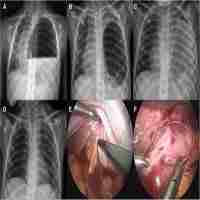

| Abstract | Tension gastrothorax in children is a life-threatening condition and presents dramatically with acute and severe respiratory distress. It develops when an intra-thoracic stomach herniated through a diaphragmatic defect is massively distended by trapped air and/or fluid causing mediastinal displacement. Tension gastrothorax is often misinterpreted as tension pneumothorax and managed as such leading to increased morbidity and mortality. We present a child with tension gastrothorax and a literature review of this phenomenon.Immediate clinical and radiographic evaluation should lead to accurate diagnosis followed by emergency decompression of the stomach before laparotomy with reduction of herniated viscera and repair of the diaphragmatic defect. |